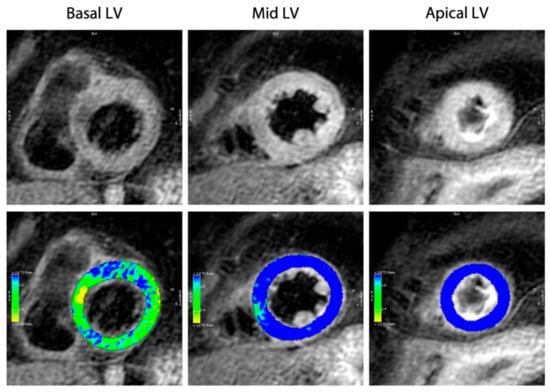

4.5. Cardiac Magnetic Resonance Imaging

| CMR (cardiac magnetic resonance) | RWMAs, RV involvement, late gadolinium-enhancement signal intensity threshold < 5 SD, and edema using T2 weighted imaging in dysfunctional LV regions. |